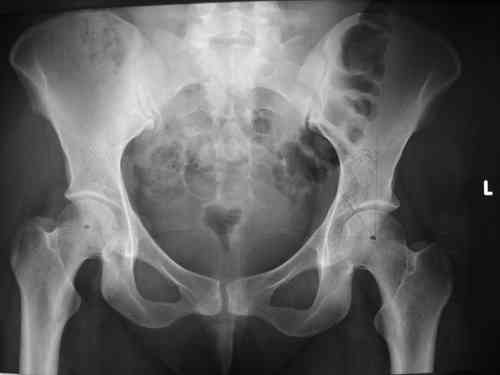

прилагаю пример с такой же давностью травмы, репонировали аппаратом

> в аппарате или одномоментно открыто. Лично я склоняюсь к аппаратному лечению на первом этапе.

> R-негативного стола. Зато новый ЭОП. Как вы проводите илиосакральные

> винты? хотябы кратенько методику.

стаскиваете пациента вниз, кладете под ноги какую-нибудь подставку, а дальше как обычно, можно , например, прочитать здесь